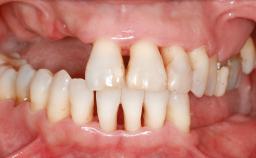

It is well known to clinicians that any removal of teeth will, over time, cause the dimensions of the alveolar ridge to be reduced by resorption of the bundle bone and by changes related to external modeling. This development is particularly evident in the crestal region with its thin buccal bone that consists of bundle bone almost entirely. The facial bone will rapidly resorb as blood supply from the periodontal ligament gets disrupted (Araújo and Lindhe 2005). There is no reason why traumatic tooth loss should not have the same consequences. It takes more than achieving implant osseointegration for a treatment outcome to be considered successful. No deficiency of bone or soft tissue is acceptable when an ideal esthetic outcome is the goal. Several articles (Sanz and coworkers 2011; Vignoletti and coworkers 2011) have reported on techniques of improving the alveolar ridge for implant treatment, notably focusing on protecting tissues from resorption.

| Bone Volume | Horizontally and vertically sufficient | Horizontally deficient | Deficient vertically or deficient vertically AND horizontally |

| Bone Volume | Deficient vertically or deficient vertically AND horizontally |